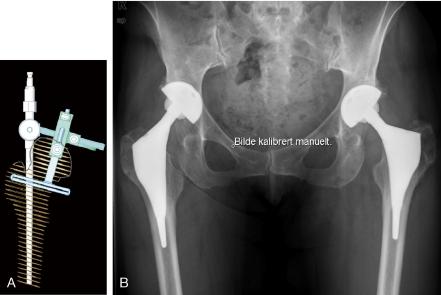

The prostheses are produced by CAD-CAM technique. The design of the stem is based on CT information, and the neck design is based on the surgeon's planning of the center of rotation, femoral head offset, and leg length correction. The first-generation stem produced before 2001 had a proximal HA coating and a sand-blasted distal part that was down-scaled to avoid contact with compact bone. The second-generation stem had a porous coating beneath the HA layer and the distal part of the stem was polished. The implant was used in 762 hips (614 patients) from 1995 until 2009. 191 of these hips were followed for 7 years and 83 others were followed for 10 years, and these hips are included in the present study. Mean age at surgery was 48 (20-65) years. Congenital dysplasia of the hip was the reason for osteoarthritis in 46% and 57% of the hips in respective groups. Merle d'Aubigné score was recorded in 152 and 75 hips in the two groups. Prostheses followed for 10 years, and almost all in the 7-year group, were first-generation stems.

假体采用 CAD-CAM 技术制造。假体柄的设计基于 CT 信息,颈的设计基于术者对旋转中心、股骨头偏心距和下肢长度校正的规划。第一代假体在 2001 年之前生产,具有近端 HA 涂层和喷砂处理的远端部分,其缩径设计避免与密质骨接触。第二代假体具有 HA 层下的多孔涂层,假体的远端部分经过抛光。1995 年至 2009 年期间,该假体应用于 762 髋(614 例患者)。其中 191 髋随访 7 年,83 髋随访 10 年,这些髋关节均纳入本研究。手术时的平均年龄为 48 岁(20-65 岁)。髋关节先天性发育不良是导致 46%和 57%髋关节发生骨关节炎的原因。两组中分别有 152 髋和 75 髋记录了 Merle d'Aubigné 评分。随访 10 年的几乎均为第一代假体,而随访 7 年的假体中第一代和第二代假体各占一半。以任何原因翻修为终点,7 年和 10 年的累计翻修率分别为 1.1%和 2.4%。7 年和 10 年时临床结果相似,Merle d'Aubigné 评分为 17 分。191 髋中有 2 髋术中发生大转子骨折(1.0%),均经钢丝环扎固定后愈合。随访 7 年时,2 髋发生假体周围骨折,均需翻修假体。1 髋在随访 7-10 年时发生 1 处骨折,经骨愈合治疗后成功。脱位率分别为 1.6%和 2.4%。随访时无影像学松动。